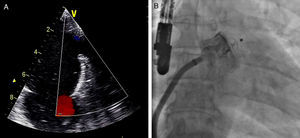

Após se satisfazerem todos estes critérios de bom posicionamento, o dispositivo foi libertado e realizou-se nova avaliação fluoroscópica e ecocardiográfica (Figura 4) para avaliar eventuais complicações imediatas, como deslocamento ou migração do dispositivo, formação de trombo intracardíaco ou adjacente ao dispositivo, derrame pericárdico, compressão da artéria circunflexa ou da veia pulmonar superior esquerda, ou a presença de fluxo residual. No caso de estes critérios não se encontrarem satisfeitos, o dispositivo deveria ser total ou parcialmente recapturado e reposicionado antes de ser libertado.